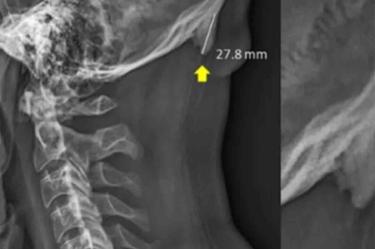

Una investigación publicada en la revista Journal of Anatomy reveló que el uso de los teléfonos celulares está provocando la salida de una especie de cuerno en el cráneo humano.

David Shahar, científico encargado de la investigación, reveló que existe una tendencia al crecimiento de una pequeña protuberancia en forma de pico en el cráneo humano.

Este bulto, indica, puede sentirse al tacto y, con la calvicie, puede resultar visible a simple vista.

Para este trabajo, el investigador de la Universidad de Sunshine Coast, en Australia, revisó a 218 personas de entre 18 y 20 años de edad, en el año 2016.

Un 41% de los sujetos muestra revelaron el pequeño pico de más de 10 milímetros.